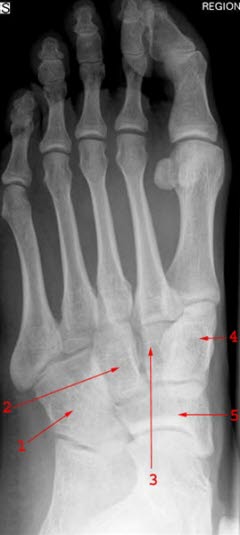

Røntgenundersøkelser er ikke nødvendig ved plattfot annet enn i de tilfellene hvor det foreligger stiv plattfot og pasienten plages med smerter.

Stiv plattfot fører ofte til plager ved økende alder og økende aktivitet. Spesialtilpassede såler (myke fotsenger) kan være aktuelt ved stiv plattfot. Ved vedvarende plager kan utredning med CT og/eller MR være aktuelt. Ved skjelettskader eller nerve og muskelsykdom kan operasjon i foten være aktuelt.